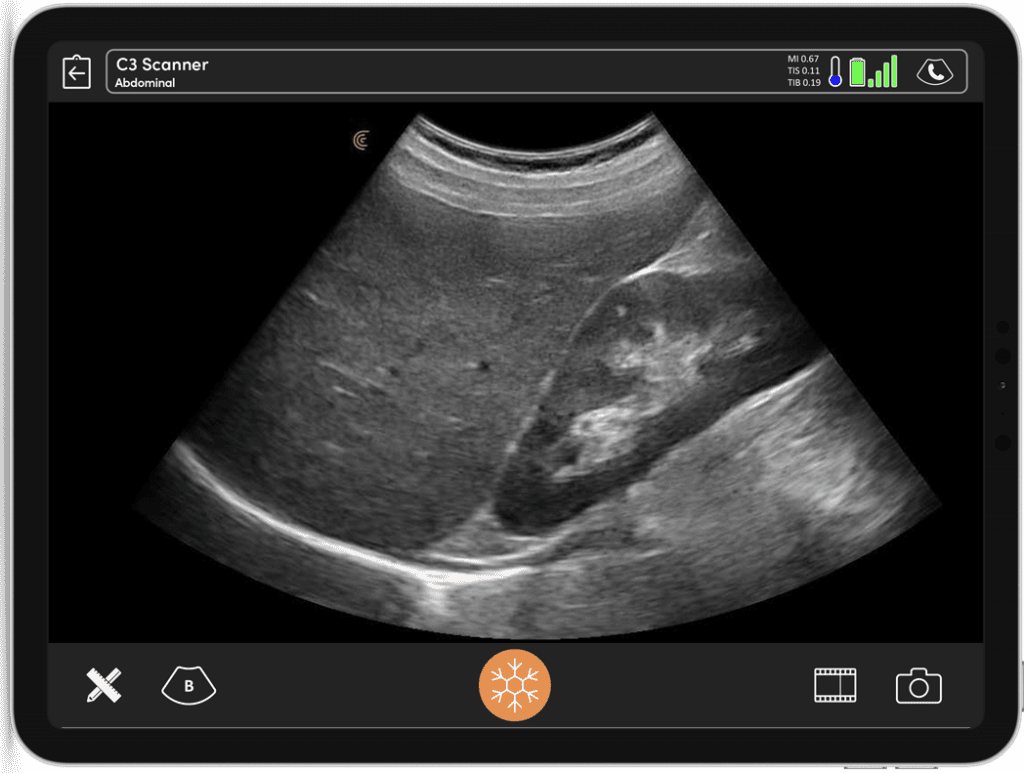

As ultrasound systems have become affordable and easier to use, general practitioners are now using point-of-care ultrasound (POCUS) for faster diagnosis and more accurate treatment plans. With superior image quality, Clarius wireless scanners enable fast confirmation of a clinical diagnosis without requiring a referral. Common exams include the review of specific organs, scanning for gall stones, screening for abdominal aortic aneurysm, lung scans for pneumonia, liver scans for fibrosis, and identifying or ruling out ectopic pregnancy among other obstetric applications.

First and foremost, the high-quality imaging is what I love about the Clarius Scanner.

I love the fact that it’s cordless. The picture itself is amazing, and I love the fact that I can increase the depth with a simple flick of the finger.

Clarius is the future of patient care. The image quality is amazing for any scanner, much less one that fits in my pocket.

Despite its small size, the Clarius scanner has an image quality that is comparable to my standard ultrasound device in practice.